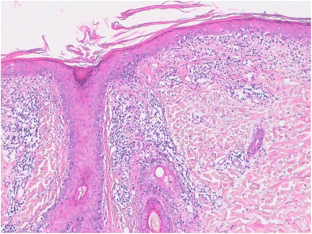

Crowson AN, Magro C (2001) The cutaneous pathology of lupus erythematosus: a review. J Cutan Pathol 28(1):1–23